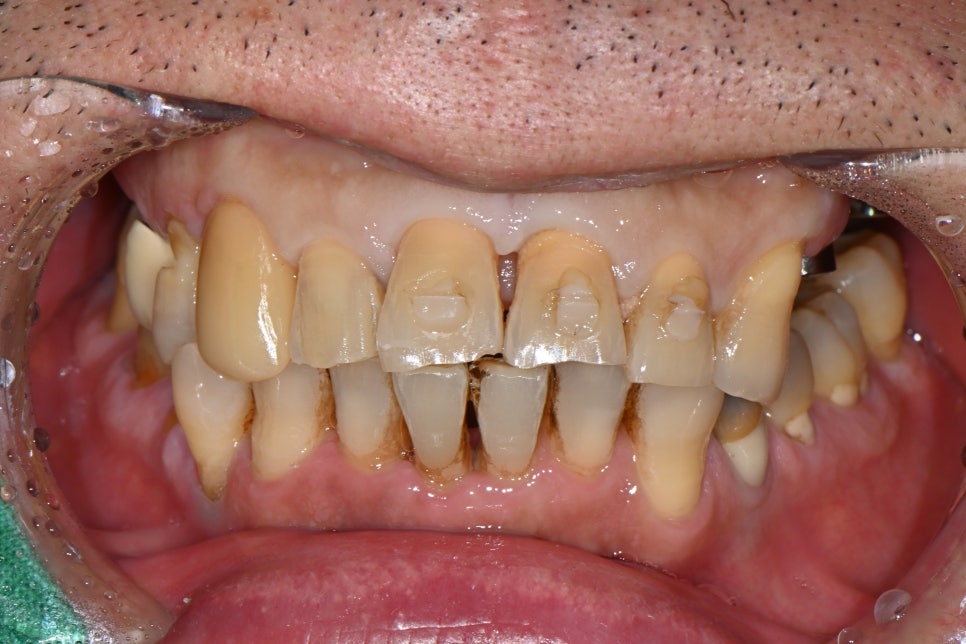

⏳ 총 치료기간 약 6개월

환자분과의 여정은 약 6개월간 이어졌습니다.

초기 외상 치료부터 시작해,

중간중간 잇몸 치료와 스케일링 등 구강위생 개선까지 꼼꼼히 병행하며

전체적인 구강 건강을 끌어올릴 수 있었습니다.

🖼️ 치료 전 후 비교 사진

치료 전후 파노라마 X-ray 비교 사진 (왼쪽: 초진 / 오른쪽: 치료 후)

환자분도 치료 내내 꾸준히 내원해주셨고,

저희도 각 단계마다 최선을 다해 도와드린 덕분에

사고 이전보다 더 건강한 구강 상태로 회복된 사례였습니다.